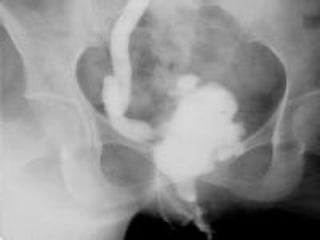

BLADDERBLADDER

Descending infection to bladderDescending infection to bladder

HealingHealing

small, contracted bladder with greatly thickened wallssmall, contracted bladder with greatly thickened walls

(thimble bladder)(thimble bladder)

three functional consequencesthree functional consequences

-small bladder capacity-small bladder capacity

-incomplete emptying with sec. bacterial infection-incomplete emptying with sec. bacterial infection

-vesicoureteral reflux (Golf hole)-vesicoureteral reflux (Golf hole)